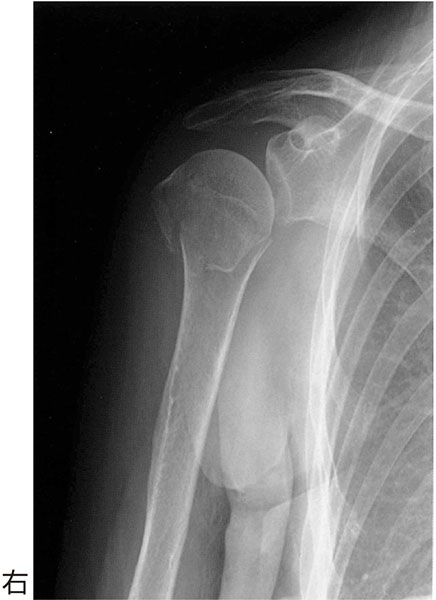

60歳の女性.転倒して右肩関節痛を訴えた.エックス線写真を下に示す.まず患部に

- 1.ギプス固定

- 2.極超短波治療

- 3.三角巾固定

- 4.髄内釘固定

- 5.超音波治療

解答: 3